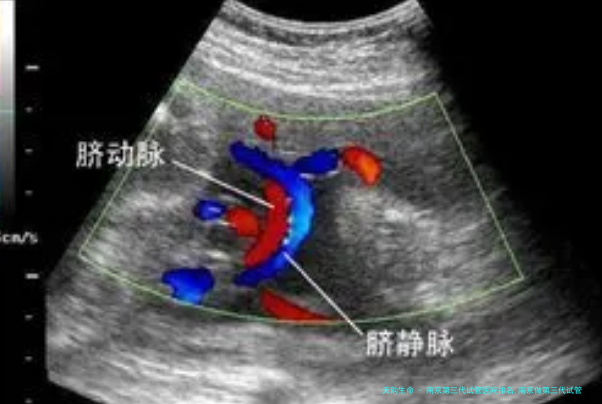

在B超引导下经阴道穿刺促排。